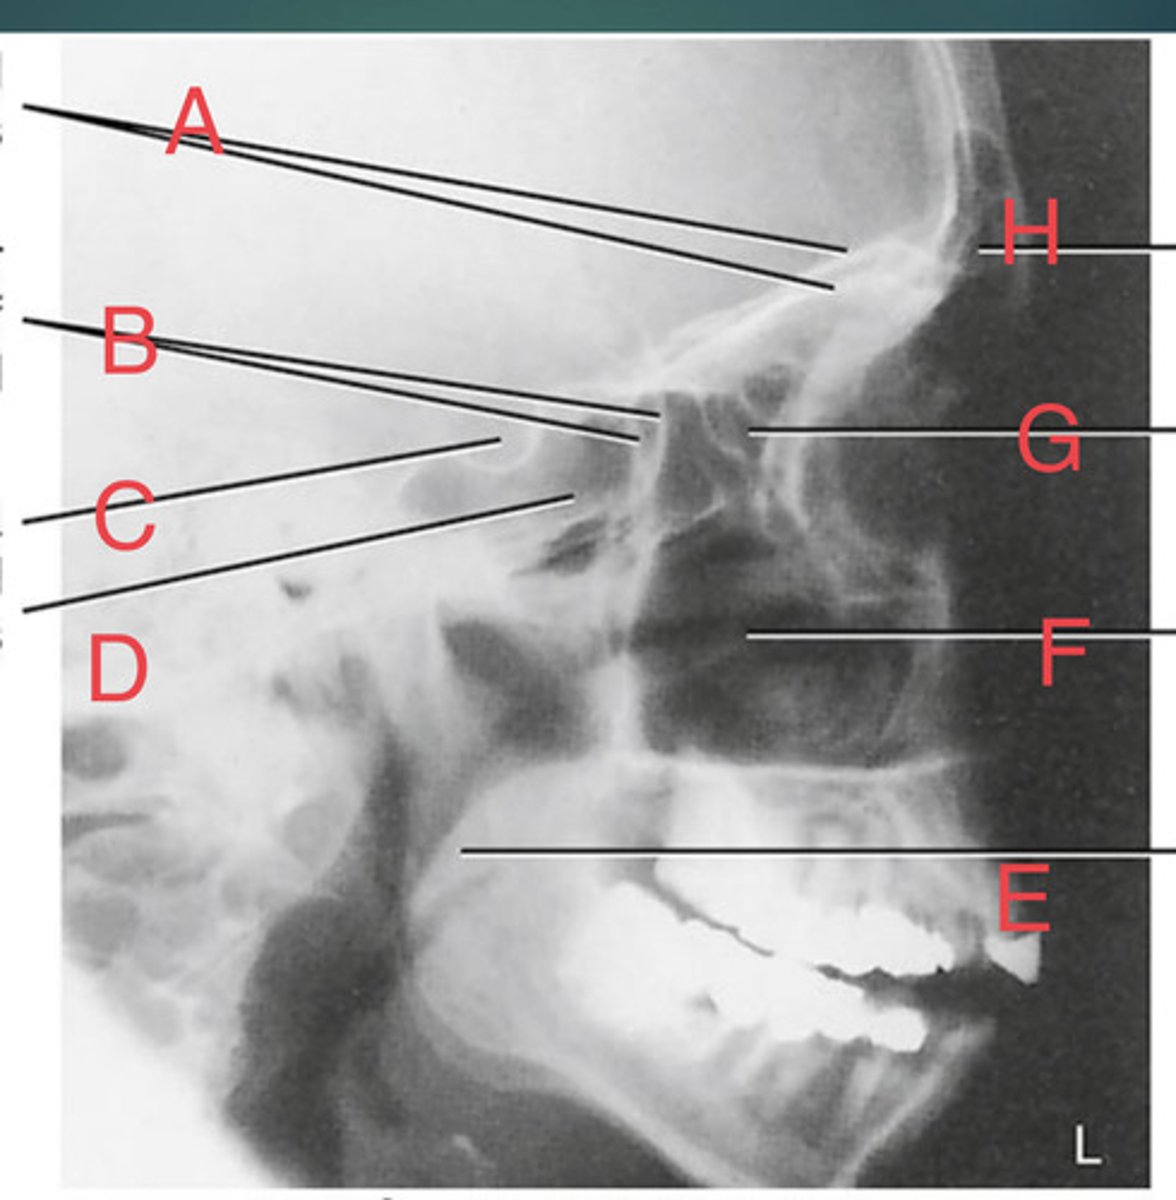

Lateral sinus

What position?

L. Orbital roofs

A.

L. Greater wings of sphenoid

B.

sella turcica of sphenoid

C.

L. Sphenoid sinus

D.

L. Rami of mandible

E.

L. Maxillary sinuses

F.

L. Ethmoid sinuses

G.

L. Frontal sinuses of frontal bone

H.